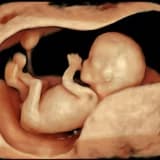

Ultrasonografi ile anne karnında bebeğin cinsiyetinin tespitinin gebelik haftasına bağlı olarak mümkün olduğunu belirten Kadın Hastalıkları ve Doğum Uzmanı Op. Dr. Filiz Candan Topuz, erken gebelik haftasında cinsiyet belirlenmesinin bakılan ultrasonografi cihazının gelişmişliğiyle de ilgili olduğunu kaydediyor. Yaklaşık 13-16 gebelik haftasında cinsiyetin görülebileceğini söyleyen Topuz, özellikle erkek bebeklerin erken tanınabildiğini ifade ediyor. Ancak erken gebelik haftasında genital bölgede kordonun izlenmesinin yanıltıcı olabileceğini belirten Topuz, kız bebeklerin tespitinin bu nedenle daha geç olduğunu söylüyor.

Cinsiyet tayininin gerekli olduğu bazı zorunlu durumlardan söz eden Topuz, ailesinde hemofili, renk körlüğü ve kas erimesi (Duchenne tipi kas distrofisi) gibi X kromozomuna bağlı geçen otozomal resesif hastalıkları taşıyan gebelerde, bebeğin bu hastalıkları taşıyıp taşımadığının belirlenmesi için cinsiyet tayini gerektiğini kaydediyor. Bu hastalıklarda annenin taşıyıcı olduğunu belirten Topuz, hastalığın erkek çocukta ortaya çıktığını ifade ediyor.

Cinsiyeti prenatal tanı testleri, amniosentez (amnios suyunun incelenmesi) ve CVS (plasentadan biopsi alınması) ile kesin olarak saptamanın mümkün olduğunu söyleyen Topuz, ancak bu şekilde fetusun cinsiyetinin belirlenmesine bahsettiği durumlarda izin verildiğini belirtiyor.